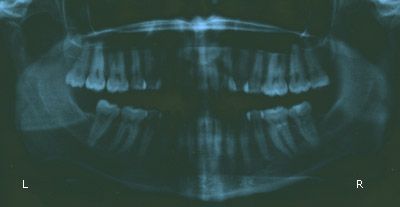

Tuesday 8/1: Dentist visit

My dentist visit was not as bad (or as expensive) as I had feared, in that I didn’t have to get another filling, so that was a relief! He placed a “surface adhesive restoration posterior” on the side of the tooth that had been troubling me (right mandibular first molar); the gum was a bit receded from it or something, and the black on the top was just some discoloration. He also removed the usual calculus buildup on my bottom front teeth, which was rather painful! He said my saliva is very alkaline, which is why I get the buildup. Other than that my teeth were reasonably healthy and that my oral hygiene was good.